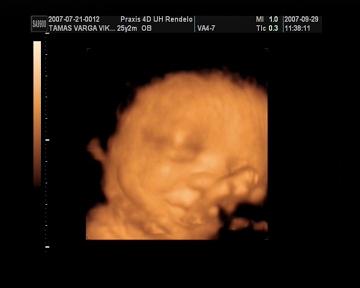

Megjöttünk az uh-ról. Jelentem óriásbébivel rendelkezem! Néhány adat a sok-sok közül: BPD: 8,84 cm AC:29,1 cm FL: 5,94 cm. Becsült súly: 2057 g. Mért adatok alapján becsült terhességi hét: 33.hét 5. nap. :) Úgyhogy Bendő két héttel előrébb jár kb. Viszont hosszban nem olyan hosszú, 40 cm körül van.

Azt mondta a doki bácsi, hogy teljesen egészségesnek tűnik és nagyon szép. Teszek fel képet!

Viki! Tényleg nagyon szép a kissrác! A második képen olyan, mintha magában mulatna valamin :wink: És a méretei nem semmik :shock: Látom, a Praxisban voltatok. Nagyon megbízhatóan, megnyugtatóan át szokták nézni a babákat, nem csak moziznak, és ez jó szerintem.

Varga Viki:Nagyon édes a kisfiad, a második képen mintha elmosolyodott volna.Mi szerdán voltunk ultrahangon a 32.héten járunk akkor volt 2130g és 42cm és azt mondt a doki, hogy átlagos baba, de szerintem óriás bébi lesz.Szedtél valami vitamint?